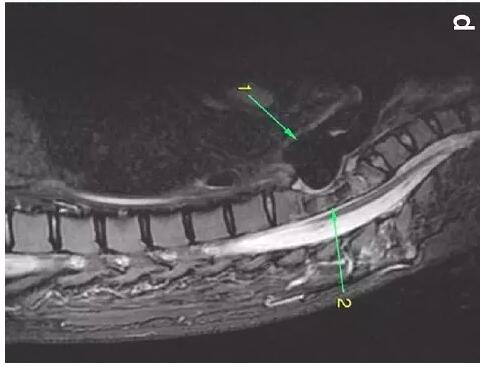

患者入住我院前行胸MRI已經(jīng)發(fā)現(xiàn)類似表現(xiàn)(圖d)��,當(dāng)時診斷為骨髓炎��。

下圖箭頭1為氣切套管氣囊緊貼T1-4椎體水平��,造成椎體前部受到侵蝕(箭頭2):